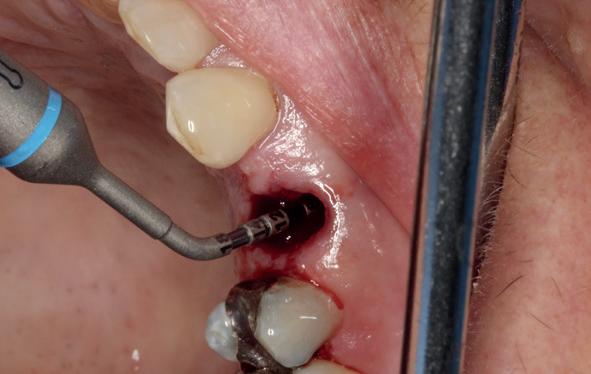

Afbeelding 1 en 2. Een immediate placement (afbeelding 1) is maar weinig invasief en zal weinig nalast geven. Bij een uitgebreide botopbouw (afbeelding 2) daarentegen is de wond veel groter en kan er meer nalast verwacht worden.

In deze casus is extractie van de 37 geïndiceerd in verband met een fistel en restpockets, zoals zichtbaar op de röntgenfoto’s (afbeelding 1). Duidelijk te zien is de forse peri-apicale ontsteking en het botverlies bij de 37, dat zowel richting buccaal als linguaal doorloopt. De 37 wordt atraumatisch verwijderd. Er is aan de linguale zijde veel bot verloren en er is sprake van een perforatie aan de buccale zijde.

Er wordt besloten om botmateriaal te plaatsen in de extractie-alveole. Vervolgens wordt het afgesloten met een titanium versterkt d-PTFE membraan (afbeelding 2). Na vier weken wordt het membraan verwijderd.